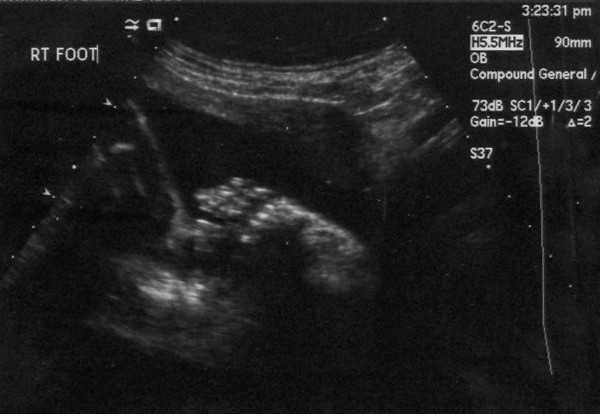

Here is a foot.

Here is the right foot. All five toes were there. It was rather difficult to get a picture of the left foot for a few reasons, not the least of which being that Junior was moving like crazy.